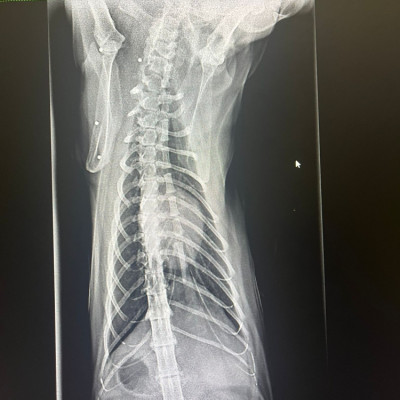

Lo rescatamos desde Francia, y, al llegar aquí, nos encontramos con este panorama desolador para él:  una auténtica barbaridad de perdigones en el cuerpo y una cardiopatía ❤️‍🩹 Las imágenes hablan por sí solas...